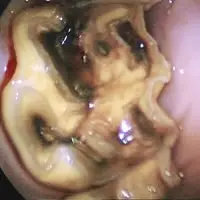

- Maulhöhlenendoskopie